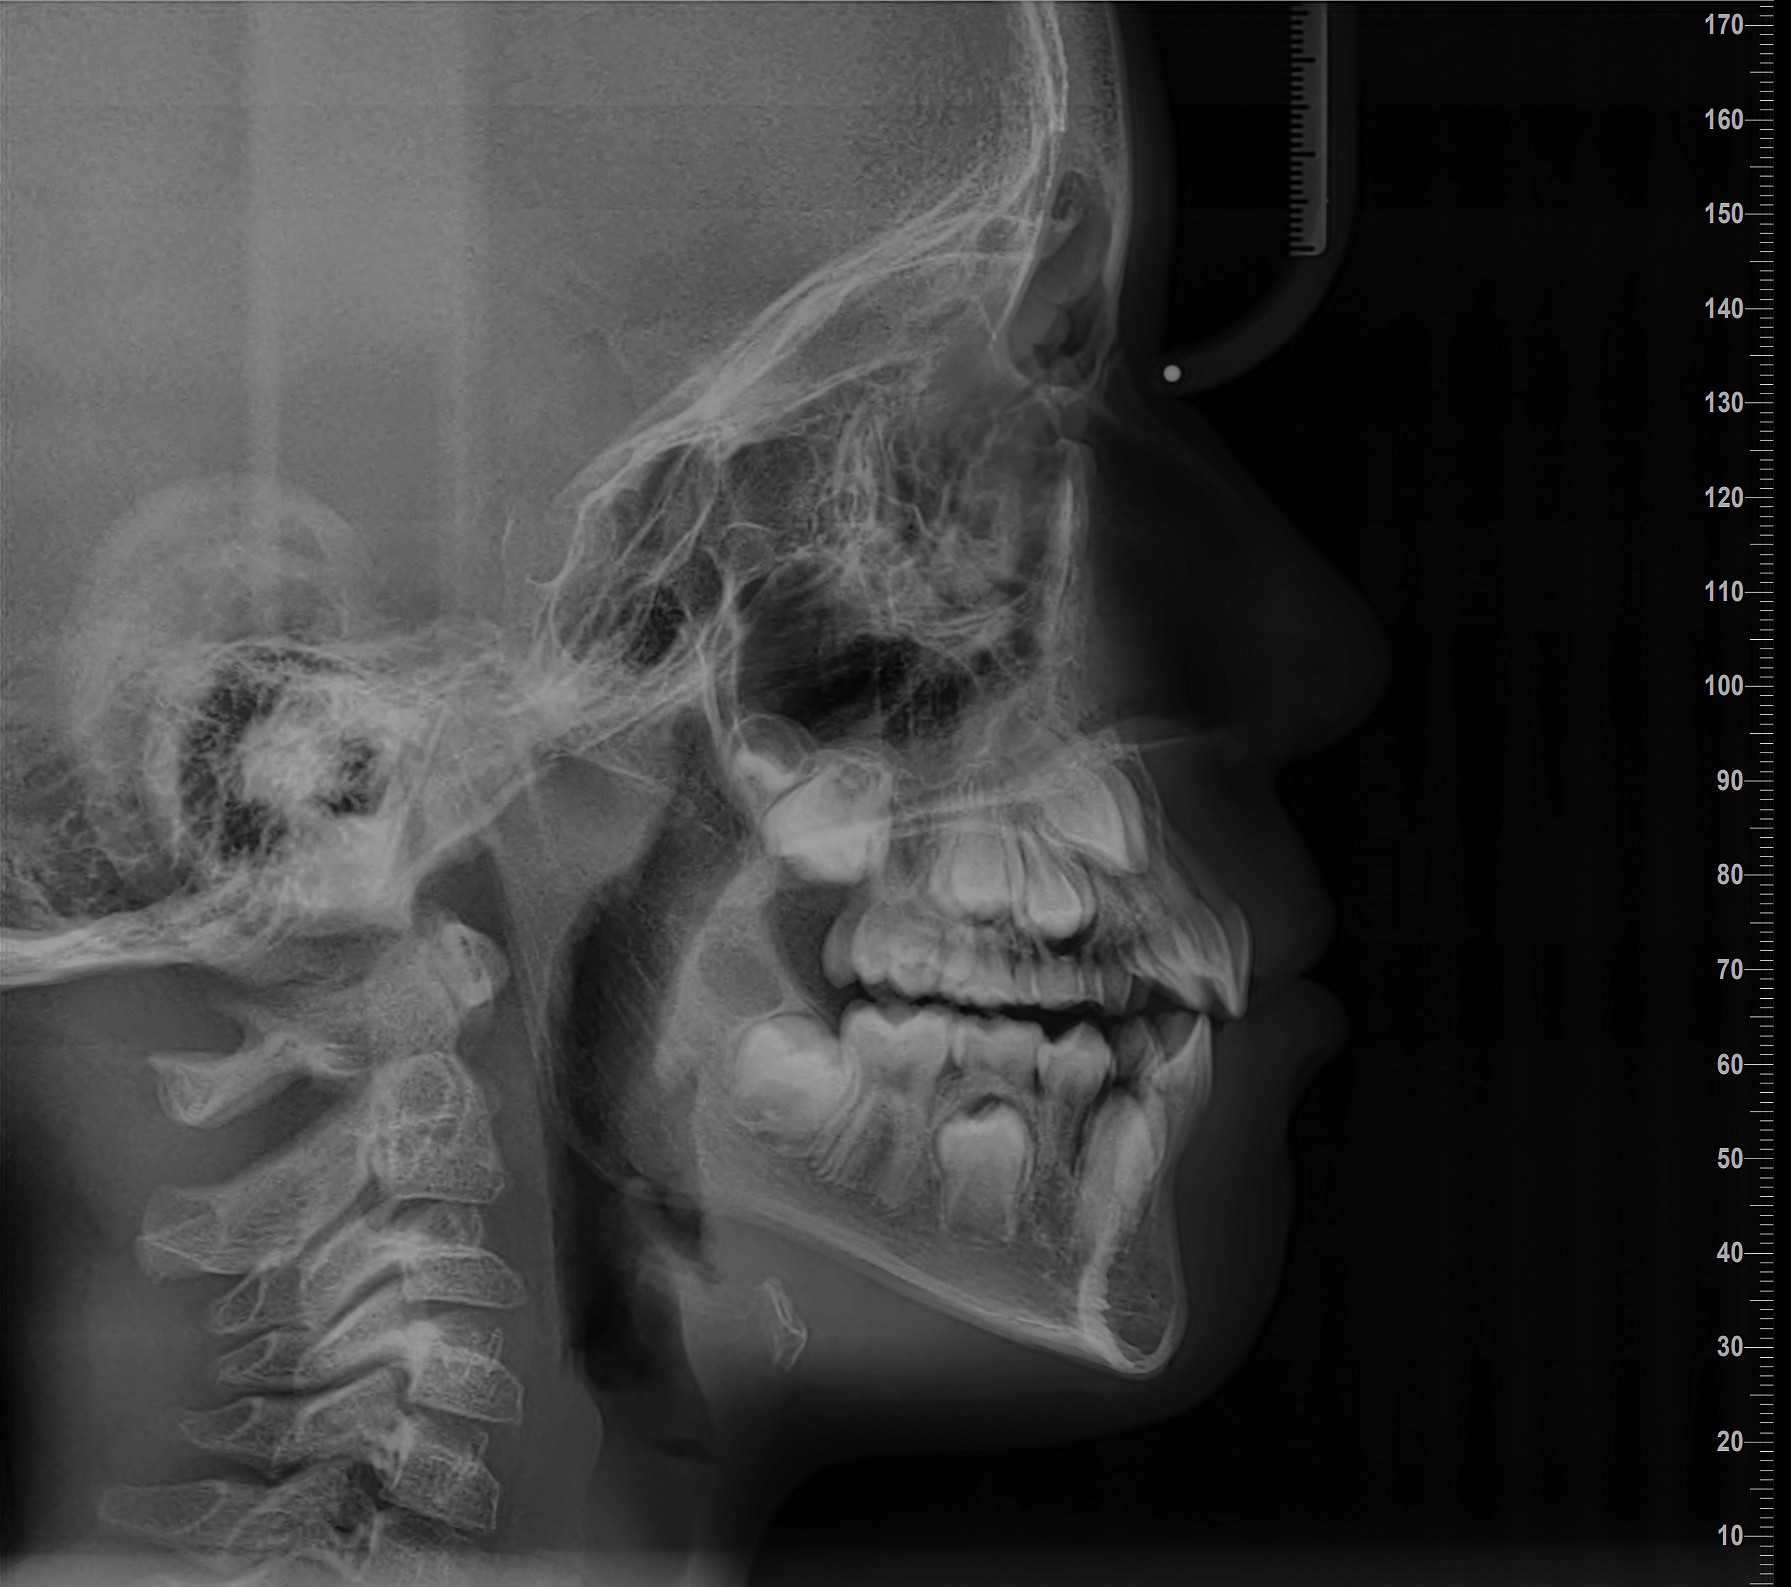

ΨΗΦΙΑΚΗ ΠΛΑΓΙΑ ΚΕΦΑΛΟΜΕΤΡΙΚΗ ΑΚΤΙΝΟΓΡΑΦΙΑ

Η πλάγια κεφαλομετρική ακτινογραφία είναι μια τυπική πλάγια ακτινογραφία του κρανίου, η οποία λαμβάνεται με σταθερές συνθήκες λήψης, που είναι δυνατόν να επαναλαμβάνονται με ακρίβεια οποτεδήποτε χρειαστεί, ώστε να μελετάται η πορεία ανάπτυξης του προσώπου.. Αποτελεί το σημαντικότερο μέσο μελέτης και διερεύνησης της αύξησης του κρανιοπροσωπικού συμπλέγματος.

Η πλάγια κεφαλομετρική ακτινογραφία χρησιμοποιείται κυρίως στην ορθοδοντική για τον ακριβή προσδιορισμό αποστάσεων και γωνιών μεταξύ των οστών των γνάθων και των μαλακών μορίων του προσώπου. Με αυτή μπορεί επίσης να μελετηθεί η σχέση μεταξύ των οστικών μορίων (άνω και κάτω γνάθος), η σχέση μεταξύ των δοντιών και η σχέση μεταξύ των οστικών μορίων και των δοντιών. Επίσης, μπορεί να μελετηθεί η θέση και η σχέση των μαλακών μορίων (χείλη, μύτη κλπ) ως προς το οδοντοσκελετικό υπόστρωμα του προσώπου.